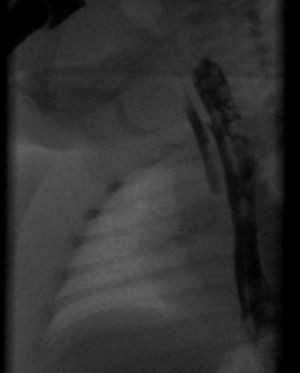

영아는 출생 첫날 첫 수유 후 삼키는 데 실패하면 기관식도샛길(TEF)을 의심해야 한다. 식도 폐쇄는 레일 비위관을 통해 진단할 수 있다. 레일 튜브가 위로 통과하지 못하면 식도 폐쇄와 위와 식도 사이의 소통 부재를 나타낸다. TEF는 MRI로 진단할 수 있다. TEF가 의심되는 경우 알레르기 및 심각한 난치성 흉부 감염의 위험이 높기 때문에 가스트로그래핀 조영 삼킴 검사는 사용하지 않아야 한다.